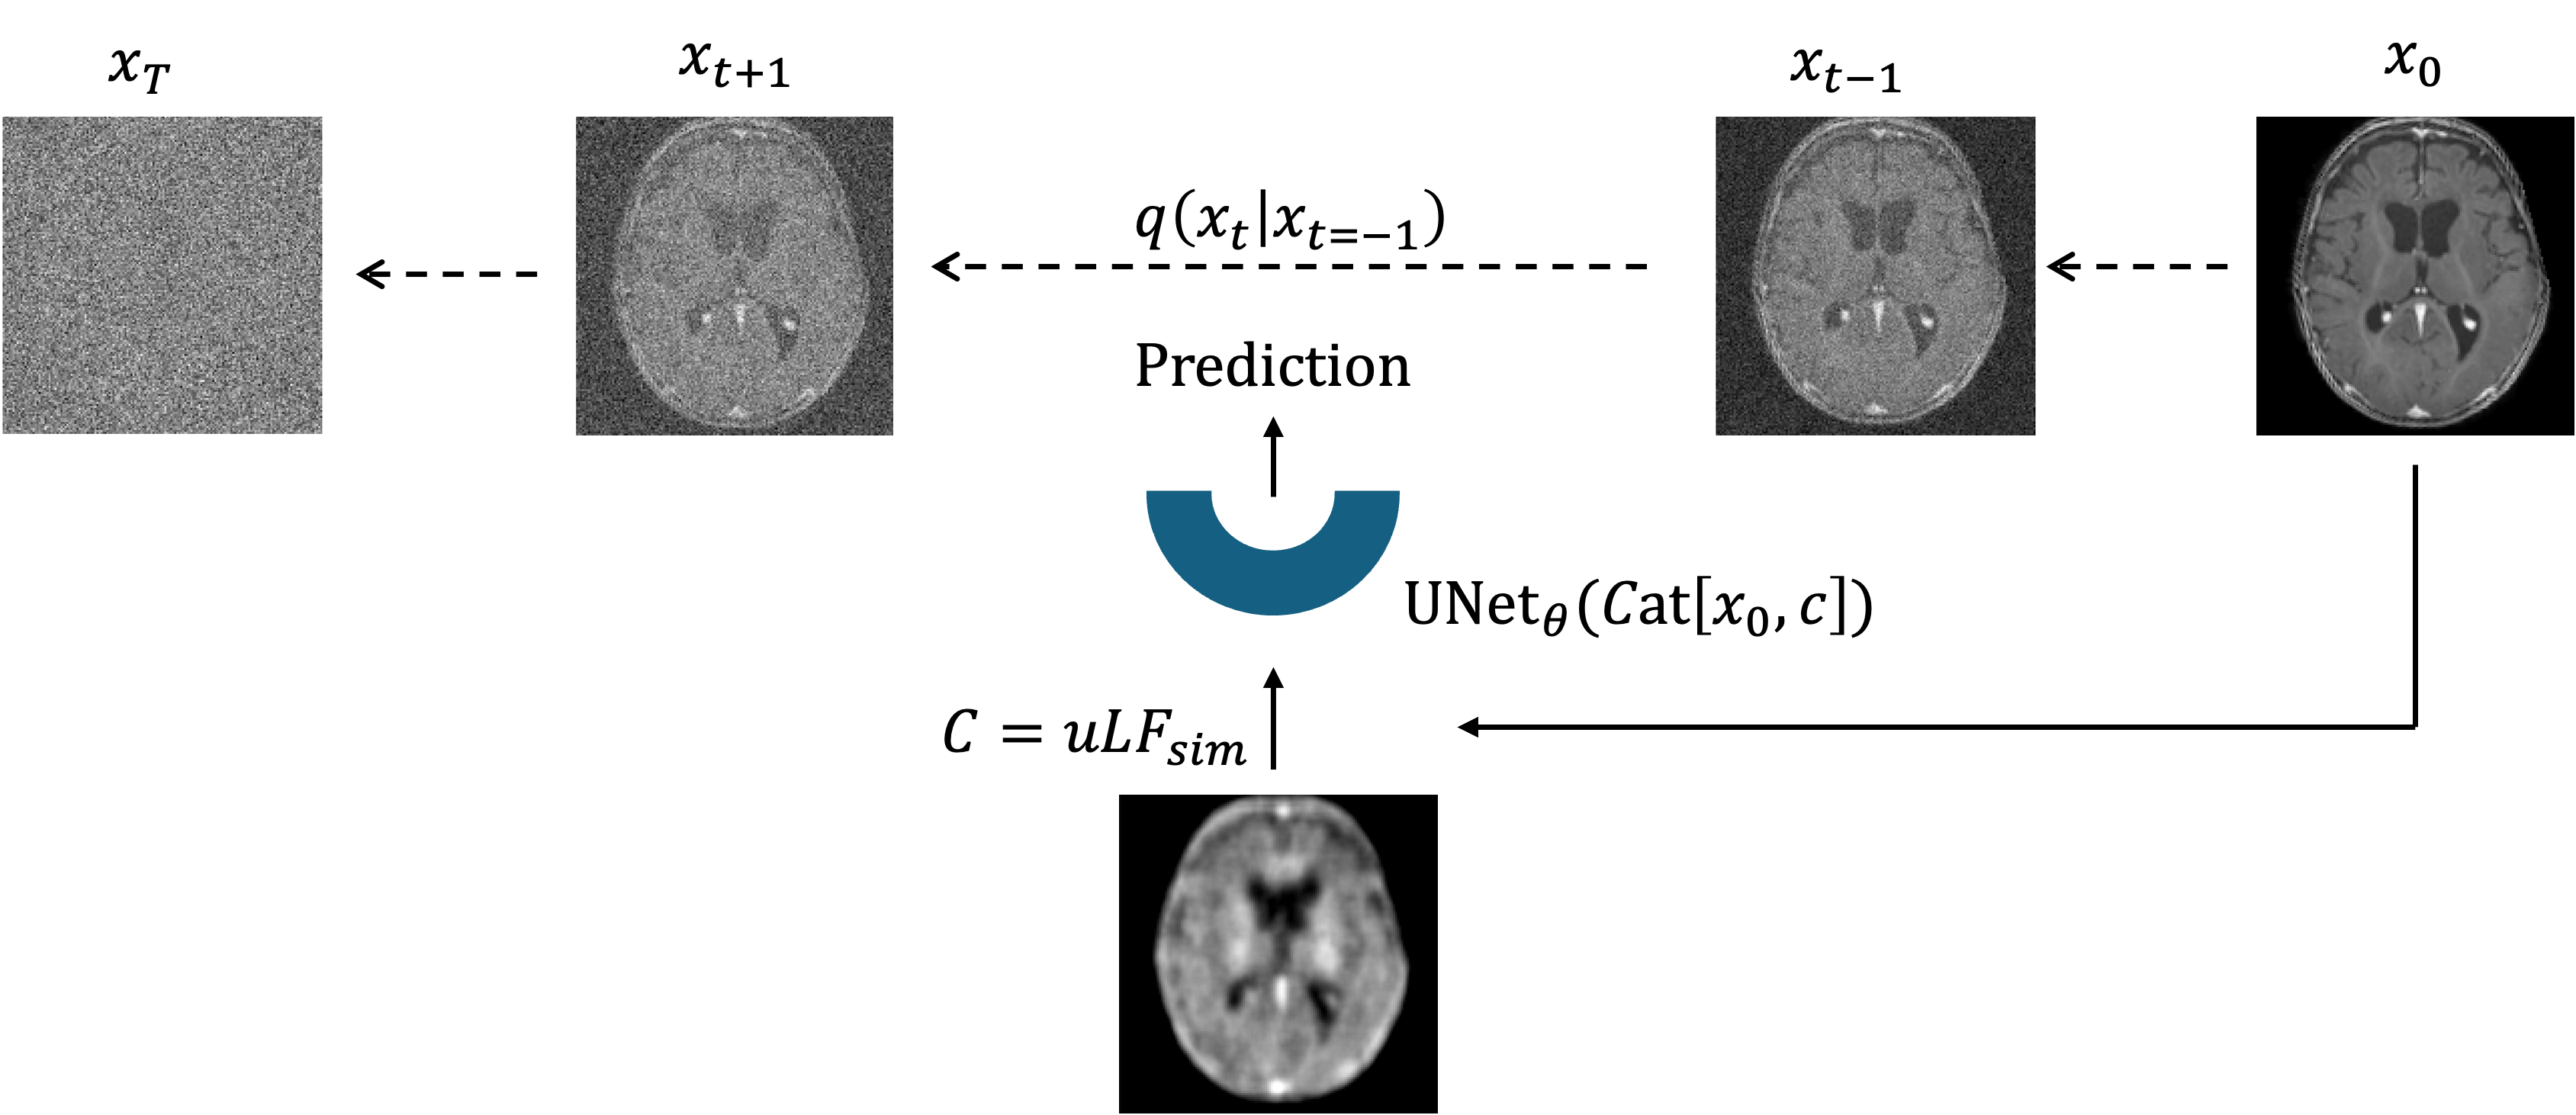

Refer to caption

((a)) Training pipeline.

((b)) Inference pipeline.

Fig. 2: Overview of the MRIQT framework showing the training (left) and inference (right) stages. Diffusion process from x0x_{0} to xTx_{T}, where x0x_{0} is HF reference and xtx_{t} is noise (\xleftarrow{}). At each timestep tTt\in T, the UNet, conditioned on c=uLFsimc=\text{uLF}_{\text{sim}} is trained to predict the added noise/v. Inference/sampling starts from x^t=Kstart=c+ϵ\hat{x}_{t=K_{start}}=c+\epsilon, where c=uLFrealc=\text{uLF}_{\text{real}}, progressively denoising the input until x0^\hat{x_{0}}.

MRIQT extends the DDPM [ho2020denoising] to 3D volumes. The forward process adds Gaussian noise xt=α¯tx0+1α¯tϵx_{t}=\sqrt{\bar{\alpha}_{t}}x_{0}+\sqrt{1-\bar{\alpha}_{t}}\epsilon (Figure 2(a)), while the reverse model learns to predict and remove the noise conditioned on the uLF input. Instead of unconditional sampling, we use image-to-image diffusion, initializing denoising from a partially noised uLF scan, which preserves structural fidelity while allowing generative refinement (Figure 2(b)), as in [saharia2022image].